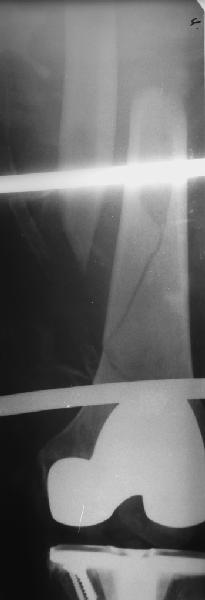

Уважаемые коллеги! 5.08.11 синтез бедренной кости пластиной LCP для дистального бедра.

Прошу совета. П-ка, 59 лет, автодорожная травма, перелом винтообразный н/3 левой бедренной кости. Планировалась закрытая репозиция и малоинвазивный доступ. по ходу операции пришлось немного открыть зону перелома для репозиции. Под контролем ЭОП вроде на столе смещение небольшое было и по оси терпимо. Сделали рентген контроль и получили вот картину. Еще обломилась головка кортикального винта. Синтез то стабильный. Только смещение не только не устранили, но кажется еще чуть больше стало (не могу) первичный снимок сделать). Склонен к ресинтезу и исправлению смещения из расширенного доступа. Как лучше выполнить репозицию? Какие можно использовать приемы репозиции? Спасибо.

конечно реостеосинтез, у Вас нижнии шуруп в линии перелома.

тип 32А1 - межфрагментарная компрессия стягивающим винтом + нейтрализующая пластина(если говорить о накостном остеосинтезе, кроме того пластинку бы подлинее этак на см 5). Ну а лучше - гвоздь с блокированием - закрыто, стабильно, с нагрузкой в послеоперационном периоде.

Коллега,для адекватной оценки перелома необходимо предоставлять предоперационные и послеоперационные снимки в двух проекциях. Насколько возможно судить по маленькой картинке прямой проекции, на первый взгляд тут простой винтообразный перелом 32-А1. В таком случае самый стабильный вариант накостного остеосинтеза - это стягивающий винт перепендикулярно линии перелома и нейтрализирующая пластина. Особых показаний к малоинвазивному мостовидному остеосинтезу нет, т.к. при нем ниже стабильность фиксации, и все микродвижения сконтрентрируются в сравнительно небольшой зоне перелома, что приведет к большим смещающим силам. Однако, если присмотрется, на снимке видно что линия перелома продолжается до начала медиального мыщелка, поэтому скорее всего это клиновидным перелом со спиральным клином 32-В1. В таких случаях возможно выполнение мостовидного синтеза, однако в данном случае дистальная часть клина не смещена относительно дистального конца бедренной кости, таким образом, мне кажется, биомеханически ситуация представляет собой среднее между А1 и чистым В1. Смещающие усилия концентрируются в проксимальной части перелома, тогда как в дистальной несмещенной части они минимальны, в т.ч. из-за интактной надкостницы. Поэтому в данном конкретном случае, при невозможности выполнения интрамедуллярного блокирующего остеосинтеза, я бы выполнил остеосинтез с двумя стягивающими винтами (с рассверливанием ближнего кортикала сверлом большего диаметра) и нейтрализирующего остеосинтеза пластиной. Причем пластина могла бы быть даже обычная.

На представленных снимках, репозиции нет, есть вальгус. Полагаю фиксация не стабильна. Перелом может и срастется, но это будет долго и без нагрузки. Если бы была использована обычная пластина, можно было бы попробовать малоинвазивно подтянуть дистальный отломок и зафиксиривовать парой винтов. Однако примененные блокирующие винты не позволят этого сделать. Как вариант, возможно открытся снизу удалить винты, сделать небольшой доступ в зоне перелома (или попробовать закрыто) ввести 1-2 винта для фиксации клина, и перепровести блокирующие дистальные винты. В любом случае, стабильность при любом из этих вариантов будет заведомо ниже чем при стягивающих винтах + нейтрализирующей пластине. Удачи.